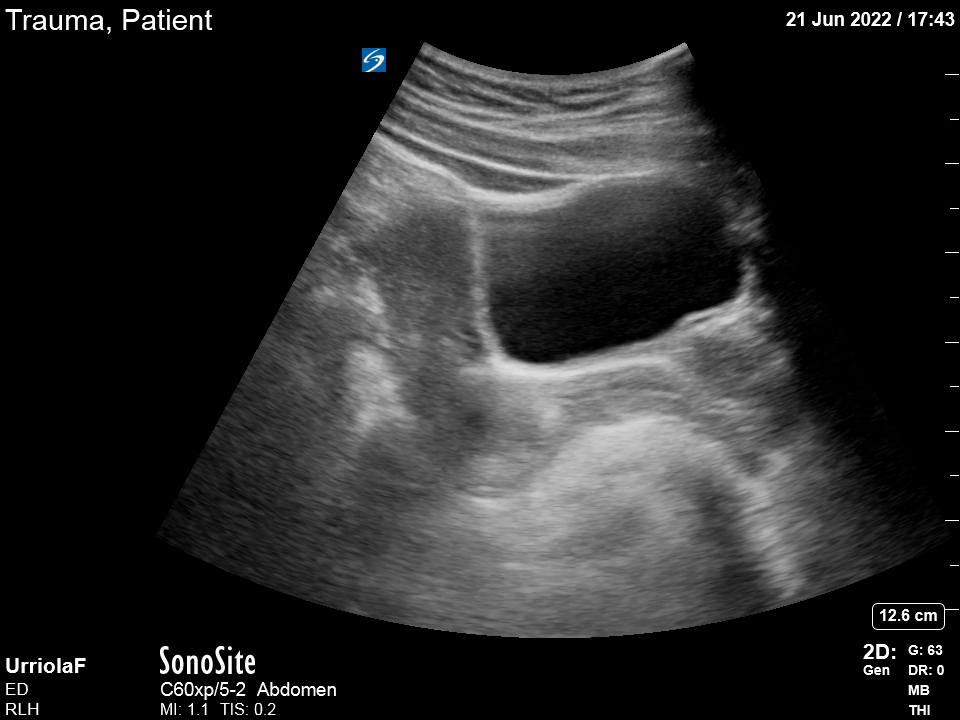

MORISON’S POUCH

This view provides a frontal (coronal) image of the abdominal right upper quadrant and requires the visualisation of the right lung base, infra-diaphragmatic space, and Morison’s pouch. The latter is the most sensitive location for detecting abdominal free fluid, which, unless clotted, appears as an anechoic (black) stripe with sharp edges. Within Morison’s pouch, the tip of the liver is the point of highest sensitivity, and it must be included in the study.

Place the probe in this area aligned with the right mid-axillary line and with the marking pointing to the patient’s head. Once the transducer is in place, the liver is utilized as an acoustic window to obtain the view, and it should demonstrate the right kidney, the liver and the diaphragm (highly echogenic). To overcome the acoustic shadows generated by the ribs, you can ask the patient to take a deep breath. Alternatively, you can gently rotate, sweep or angle the probe until a clear view of the structures is obtained.

Once everything is in order, slightly drag the probe towards cephalic to examine the lung base and liver-diaphragm interface. Then, slide back to caudal, exploring the inferior portion of the kidney and the tip of the liver.

DIFFERENTIALS

It should be considered that the presence of other abdominal structures can lead to confusion. The gallbladder, as much as renal and hepatic cysts represent anechoic structures that could be wrongly interpreted as free fluid. Is important, then, to be aware of the shape of these structures, as they have round, well-defined edges, whereas free fluid is identified by sharp edges.